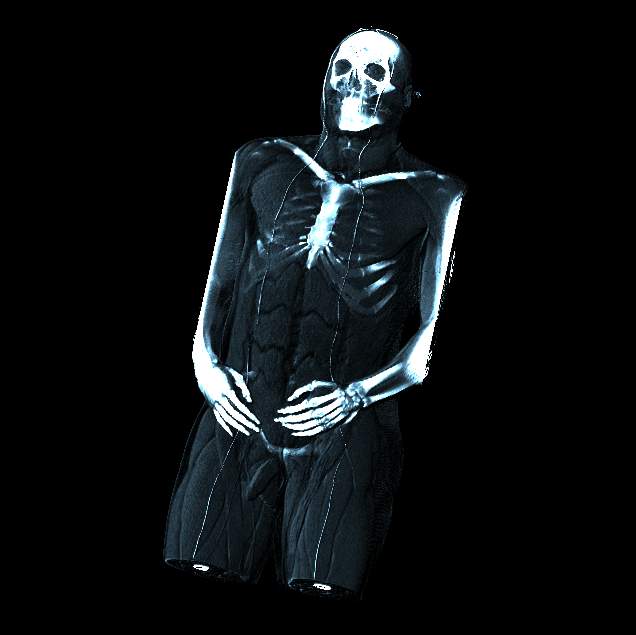

Visible human male CT data

Shaded whole

body with muscle and bone

Data Resolution : 512x512x1294